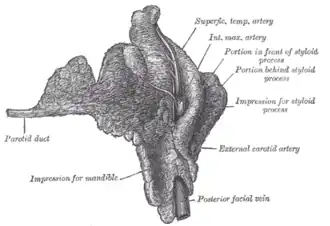

Right parotid gland. Deep and anterior aspects. (Parotid duct labeled at center left.) | |